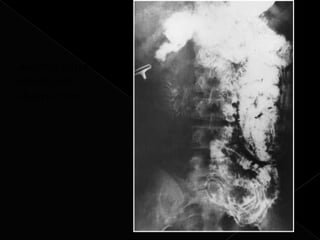

Ascaris causing

intestinal

obstruction.